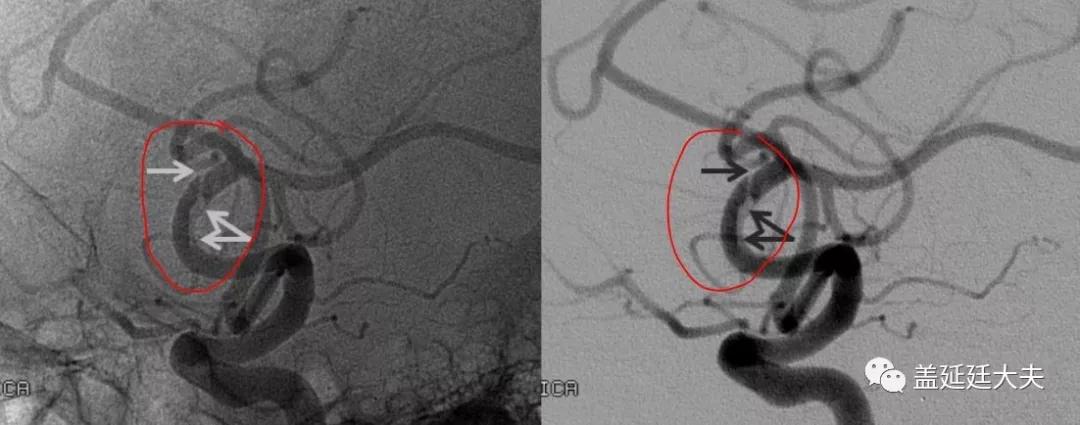

下图就是一例自愈的患者。

同样,下面这例大脑中动脉夹层由于狭窄程度只有大约40%,没有明显的临床症状只需要抗血小板治疗,随访影像检查就可以。